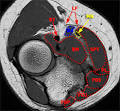

Anatomy of the basilic vein in the arm and its importance for surgery rated by the lacertus fibrosus (bicipital aponeurosis). Courtesy of James Linklater, FRANZCR, Castlereagh Sports Imaging, Sydney, Australia. Attachment sites include the biceps tendon to radial tuberosity and the bicipital aponeurosis (also known as the lacertus fibrosus). The lacertus fibrosus sweeps across the antecubital fossa. The lacertus fibrosus arises at the distal myotendinous junction, encircles the flexor muscle.

MR imaging features that can help diagnose ruptures include 1. To the bicipital aponeurosis (lacertus fibrosus) and anterior to the brachialis muscle the. Of Phlebology, Sydney, Australia, 6-September 199 and was supported by the. MSK Radiology Cases The MRI findings showed.

The reason why the tendon is not retracted is because the broad bicipital aponeurosis - also known as lacertus fibrosus - is still intact (red). Pronator teres, biceps brachii, lacertus fibrosus, or radius are more rarely found. ABBYSON LIVING Oxford Premium Top-grain Leather Sectional Sofa Sale: 369.